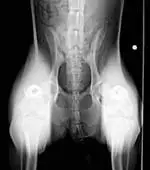

- Hip-extended ventrodorsal view to assess joint congruency (Figure 2); investigate Orthopedic Foundation for Animals (OFA) certification

- Distraction ventrodorsal or dorsoventral view to assess joint laxity (Figure 3): - PennHIP (requires certification of the veterinarian) or dorsolateral subluxation score18

(Left): Hip-extended ventrodorsal radiograph of a 10-month-old Australian shepherd with lameness and bunny-hopping gait at the run. Note the bilateral decreasedcoverage of the femoral heads by the acetabula and laxity present in the coxofemoral joints with increased severity in the left joint. (view larger image)

(Right) Ventrodorsal distraction view of the 10-month-old Australian shepherd in Figure 2. The dog’s femurs were held perpendicular to the radiography table and pressure was applied to luxate the coxofemoral joint dorsally. Note the laxity and luxation of the femoral heads from the acetabulum bilaterally. Significant bone remodeling and osteophytes are present in the left acetabulum. (view larger image)